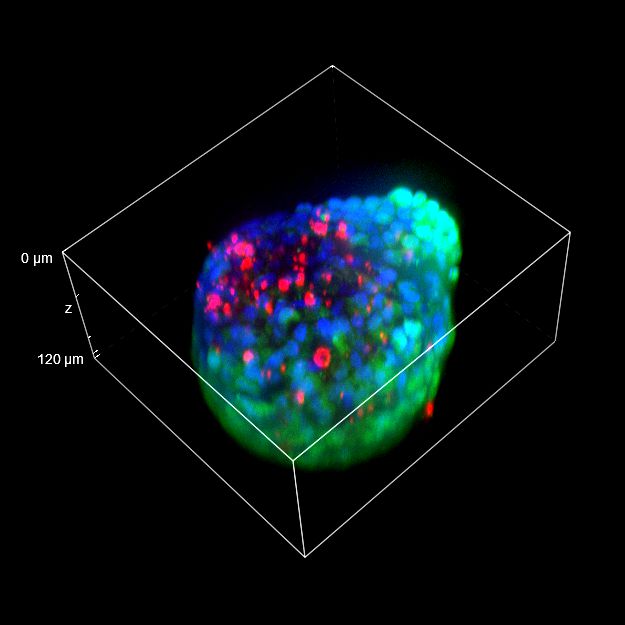

To better appreciate the 3D cellular organization, in Figure C we show a volume view (120 um thickness) of the same spheroid acquired with both objectives, showing the staining even in the deeper regions of the 3D cancer spheroid. Finally, in Figure D, a 3D movie of the whole spheroid acquired with the 25x silicone oil objective is shown.

The comparison between the images acquired with the 20x air objective and those with the 25x silicone oil objective (Figure A, B and C) highlights the importance of the lens choice based on the biological application. The transition from 20x to 25x leads to a gain in resolution (based on the greater NA of the 25x compared to the 20x NA), which certainly affects the image quality, and also leads to a reduction in the light refraction. As a matter of fact, immersion oils greatly improve the microscope’s resolving power by replacing the air gap between the lens and the coverslip with a higher refractive index medium, thus allowing to reduce the refraction of light.

In 3D imaging, matching the refractive index of the sample and its immersion medium is crucial for deep tissue observation. Silicone immersion oil is perfect for imaging through thick biological samples; it closely matches the refractive index of cells and of the mounting medium, decreasing spherical aberration and resulting in brighter and higher resolution images compared to those acquired with a common 20x air objective.

Figure C 3D tumor spheroids: 3D volume view of a spheroid acquired with 20x air objective (LEFT) and 25x silicone oil objective (RIGHT). Living cells are marked with Calcein (green) and dead cells with PI (red). Nuclei are stained with Hoechst (blue). Scale bar along Z-axis: 120 um. These images were acquired with CrestOptics X-Light V3 spinning disk.